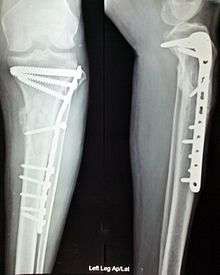

Internal fixation is an operation in orthopedics that involves the surgical implementation of implants for the purpose of repairing a bone, a concept that dates to the mid-19th century and was made applicable for routine treatment in the mid-20th century.[1] An internal fixator may be made of stainless steel or titanium.[2]

Open Reduction Internal Fixation (ORIF) involves the implementation of implants to guide the healing process of a bone, as well as the open reduction, or setting, of the bone itself. Open reduction refers to open surgery to set bones, as is necessary for some fractures. Internal fixation refers to fixation of screws and/or plates, intramedullary bone nails (femur, tibia, humerus) to enable or facilitate healing. Rigid fixation prevents micro-motion across lines of fracture to enable healing and prevent infection, which happens when implants such as plates (e.g. dynamic compression plate) are used. Open Reduction Internal Fixation techniques are often used in cases involving serious fractures such as comminuted or displaced fractures or in cases where the bone would otherwise not heal correctly with casting or splinting alone.